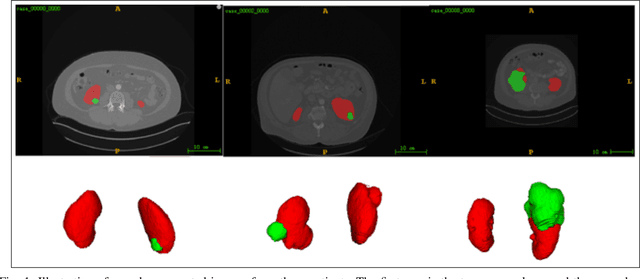

Abstract:Accurate segmentation of kidneys and kidney tumors is an essential step for radiomic analysis as well as developing advanced surgical planning techniques. In clinical analysis, the segmentation is currently performed by clinicians from the visual inspection images gathered through a computed tomography (CT) scan. This process is laborious and its success significantly depends on previous experience. Moreover, the uncertainty in the tumor location and heterogeneity of scans across patients increases the error rate. To tackle this issue, computer-aided segmentation based on deep learning techniques have become increasingly popular. We present a multi-scale supervised 3D U-Net, MSS U-Net, to automatically segment kidneys and kidney tumors from CT images. Our architecture combines deep supervision with exponential logarithmic loss to increase the 3D U-Net training efficiency. Furthermore, we introduce a connected-component based post processing method to enhance the performance of the overall process. This architecture shows superior performance compared to state-of-the-art works using data from KiTS19 public dataset, with the Dice coefficient of kidney and tumor up to 0.969 and 0.805 respectively. The segmentation techniques introduced in this paper have been tested in the KiTS19 challenge with its corresponding dataset.